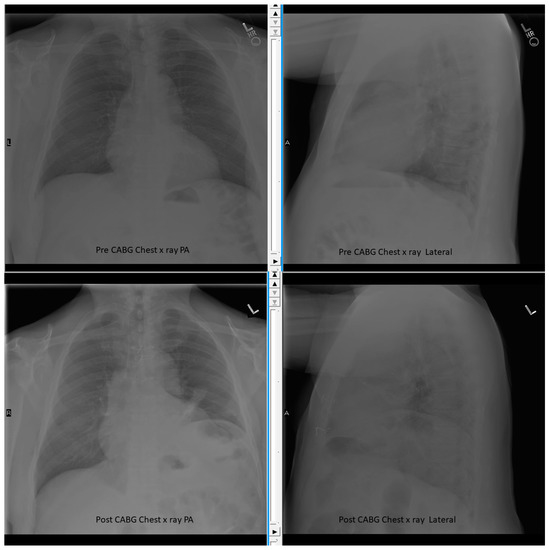

Place one hand on your abdomen and breathe deeply. Reduced number of alveoli air sacs required for normal breathing. In severe cases when there is no simple treatment that can relieve dyspnea your doctor may prescribe morphine. Congenital diaphragmatic hernia CDH. There is usually a long history of heavy smoking. Shortness of breath may be accompanied by wheezing. Diaphragmatic dysfunction caused by transverse myelitis or leukemic infiltration of the cervical spinal cord in a patient with leukemia and shortness of breath. To treat phrenic nerve irritation This condition can be managed with a breathing pacemaker which takes over the responsibility of sending messages to the diaphragm. The cause for shortness of breath was thought primarily due to stable angina on tread mill test positive finding but Chilaiditis syndrome should also be considered as a cause for the shortness of breath.

The rise in intraabdominal pressure further increases intrathoracic and lung volume by pushing the lower rib cage outward. In severe cases when there is no simple treatment that can relieve dyspnea your doctor may prescribe morphine. Diaphragmatic dysfunction caused by transverse myelitis or leukemic infiltration of the cervical spinal cord in a patient with leukemia and shortness of breath. Diaphragmatic plication a surgical procedure that pulls the diaphragm down by introducing a repeated series of continuous sutures across the diaphragm and pulling the muscle taut. A bedside fan or open window with a breeze are also simple but very effective treatments to lessen dyspnea. Depending on the severity of injury to the diaphragm some doctors recommend non-surgical options to treat the breathing issues associated with diaphragm weakness and paralysis. P E Pulmonary embolism.